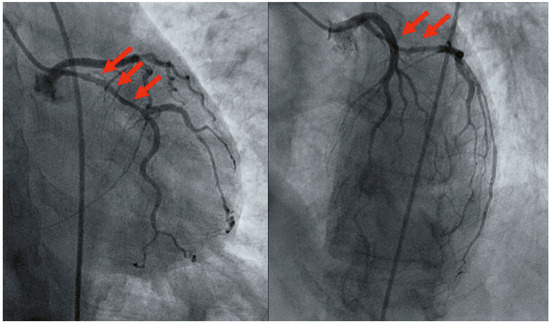

Myocardial infarction with nonobstructive coronary arteries (MINOCA): Myocardial infarction (MI) with non-obstructive coronary arteries (MINOCA) is defined as MI according to the fourth universal definition of MI [1] without coronary stenosis ≥50% on...